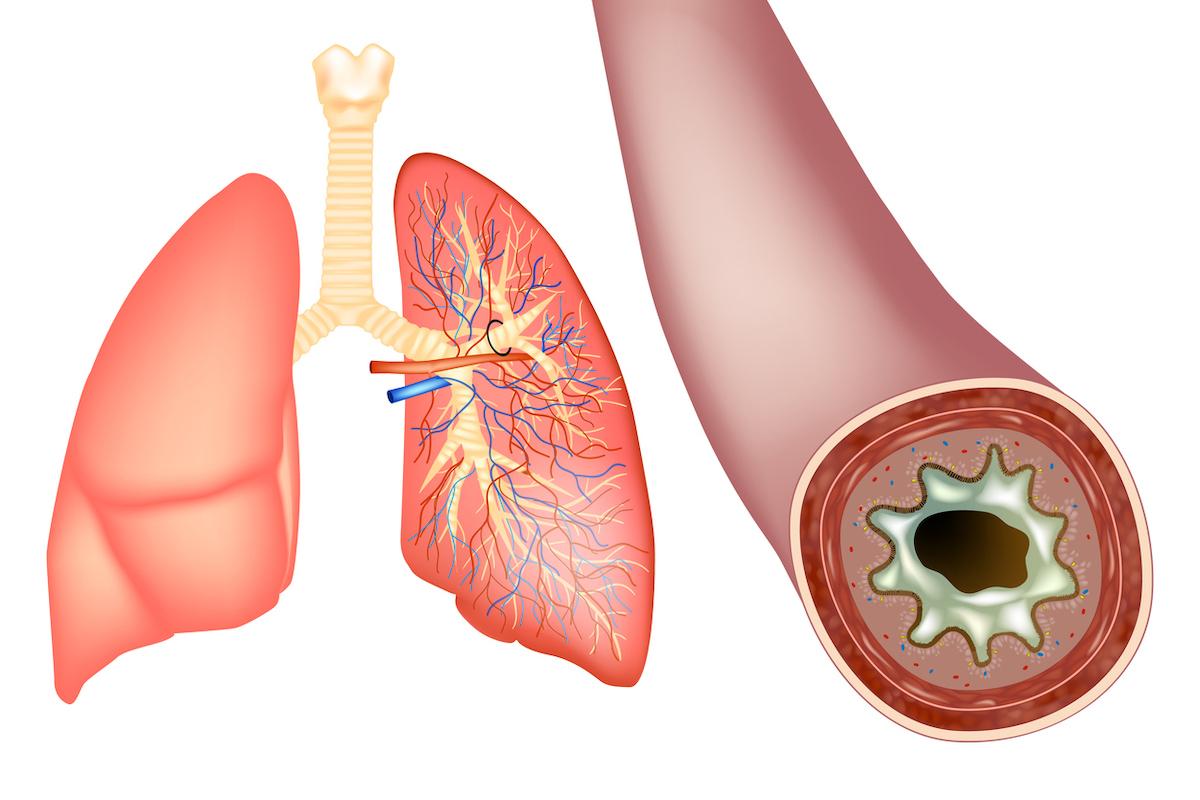

C'est une intervention doublement remarquable qui vient d'être réalisée à l'hôpital universitaire de Coventry au Royaume-Uni. Comme le raconte le quotidien Daily Mirror, un homme de 74 ans, John Smallwood, a reçu une double greffe de valves cardiaques réalisées avec des tissus de coeur de vache et cela en restant éveillé durant toute l'opération ! Habituellement les valves cardiaques greffées sont réalisées avec des tissus de porc. Mais depuis une autorisation accordée en 2004 par la FDA, celles-ci peuvent aussi être fabriquées avec du péricarde bovin, un matériau qui dure plus longtemps (15 à 20 ans) que celui issu du porc et qui, en étant de plus grand diamètre, peut s'adapter à tout patient quelle que soit sa taille.

John Smallwood, un ambulancier britannique, avait déjà subi une intervention à coeur ouvert il y a neuf ans pour une valve mitrale. Mais celle-ci a recommencé à fuir et cette fois, plus question d'une chirurgie à coeur ouvert : son état rendait très dangereuse une anesthésie générale. C'est donc sous anesthésie locale que l'opération s'est déroulée et le patient est resté réveillé durant toute l'intervention, avec le risque s'il ne restait pas parfaitement immobile de provoquer une erreur fatale. L'implantation des valves s'est faite à travers l'aine pour la valve aortique et à l'aide d'une aiguille spéciale pour passer le valve mitrale dans le coeur.